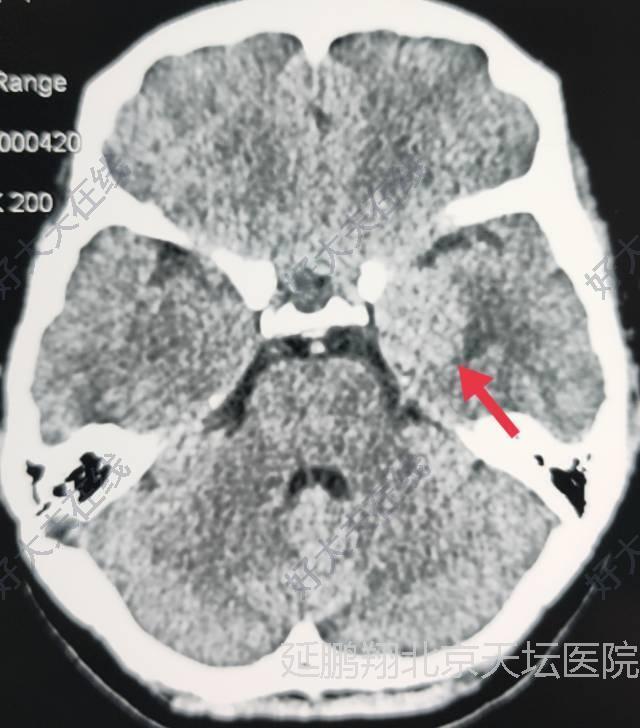

女性,48岁。发作性心悸,心烦,头晕11月。CT和MRI显示左侧鞍旁脑膜瘤,与海棉窦及颈内动脉及大脑中动脉关系密切。

术后病人全麻苏醒顺利,生命体征平稳,四肢活动好。常规术后六小时复查头颅CT显示肿瘤消失。